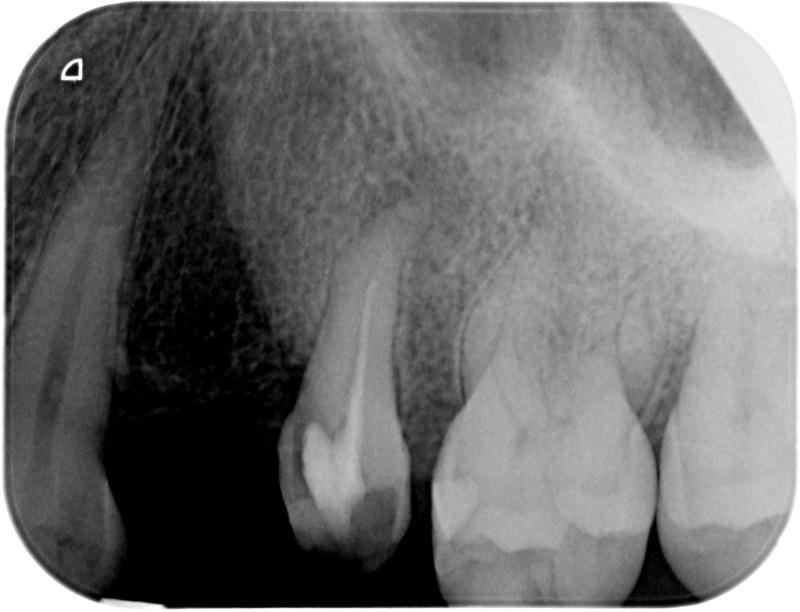

Avant

Après